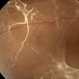

- proliferative diabetic retinopathy (PDR), NEOVASCULARISATION OF DISC

- Young Type 1 diabetic with florid neovascularisation at the optic disc.